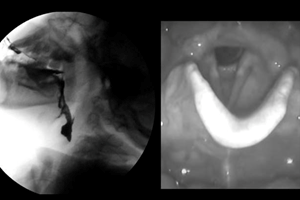

El curso en Evaluación instrumental para usuarios con trastornos de la deglución tiene como propósito brindar herramientas teóricas y prácticas sobre la evaluación videofluoroscópica, nasofibroscopía y ecografía laríngea en usuarios pediátricos y adultos que presentan trastornos de la deglución.

Este curso pretende aportar información teórica sobre la videofluoroscopía, nasofibroscopía de la deglución y la ecografía laríngea.

- Describir el fundamento teórico de los exámenes instrumentales como la videofluoroscopía, nasofibroscopía de la deglución y la ecografía laríngea y sus variantes entre la población pediátrica y adulta.

keyboard_arrow_down- Videofluoroscopía

- Nasofibroscopía de la deglución